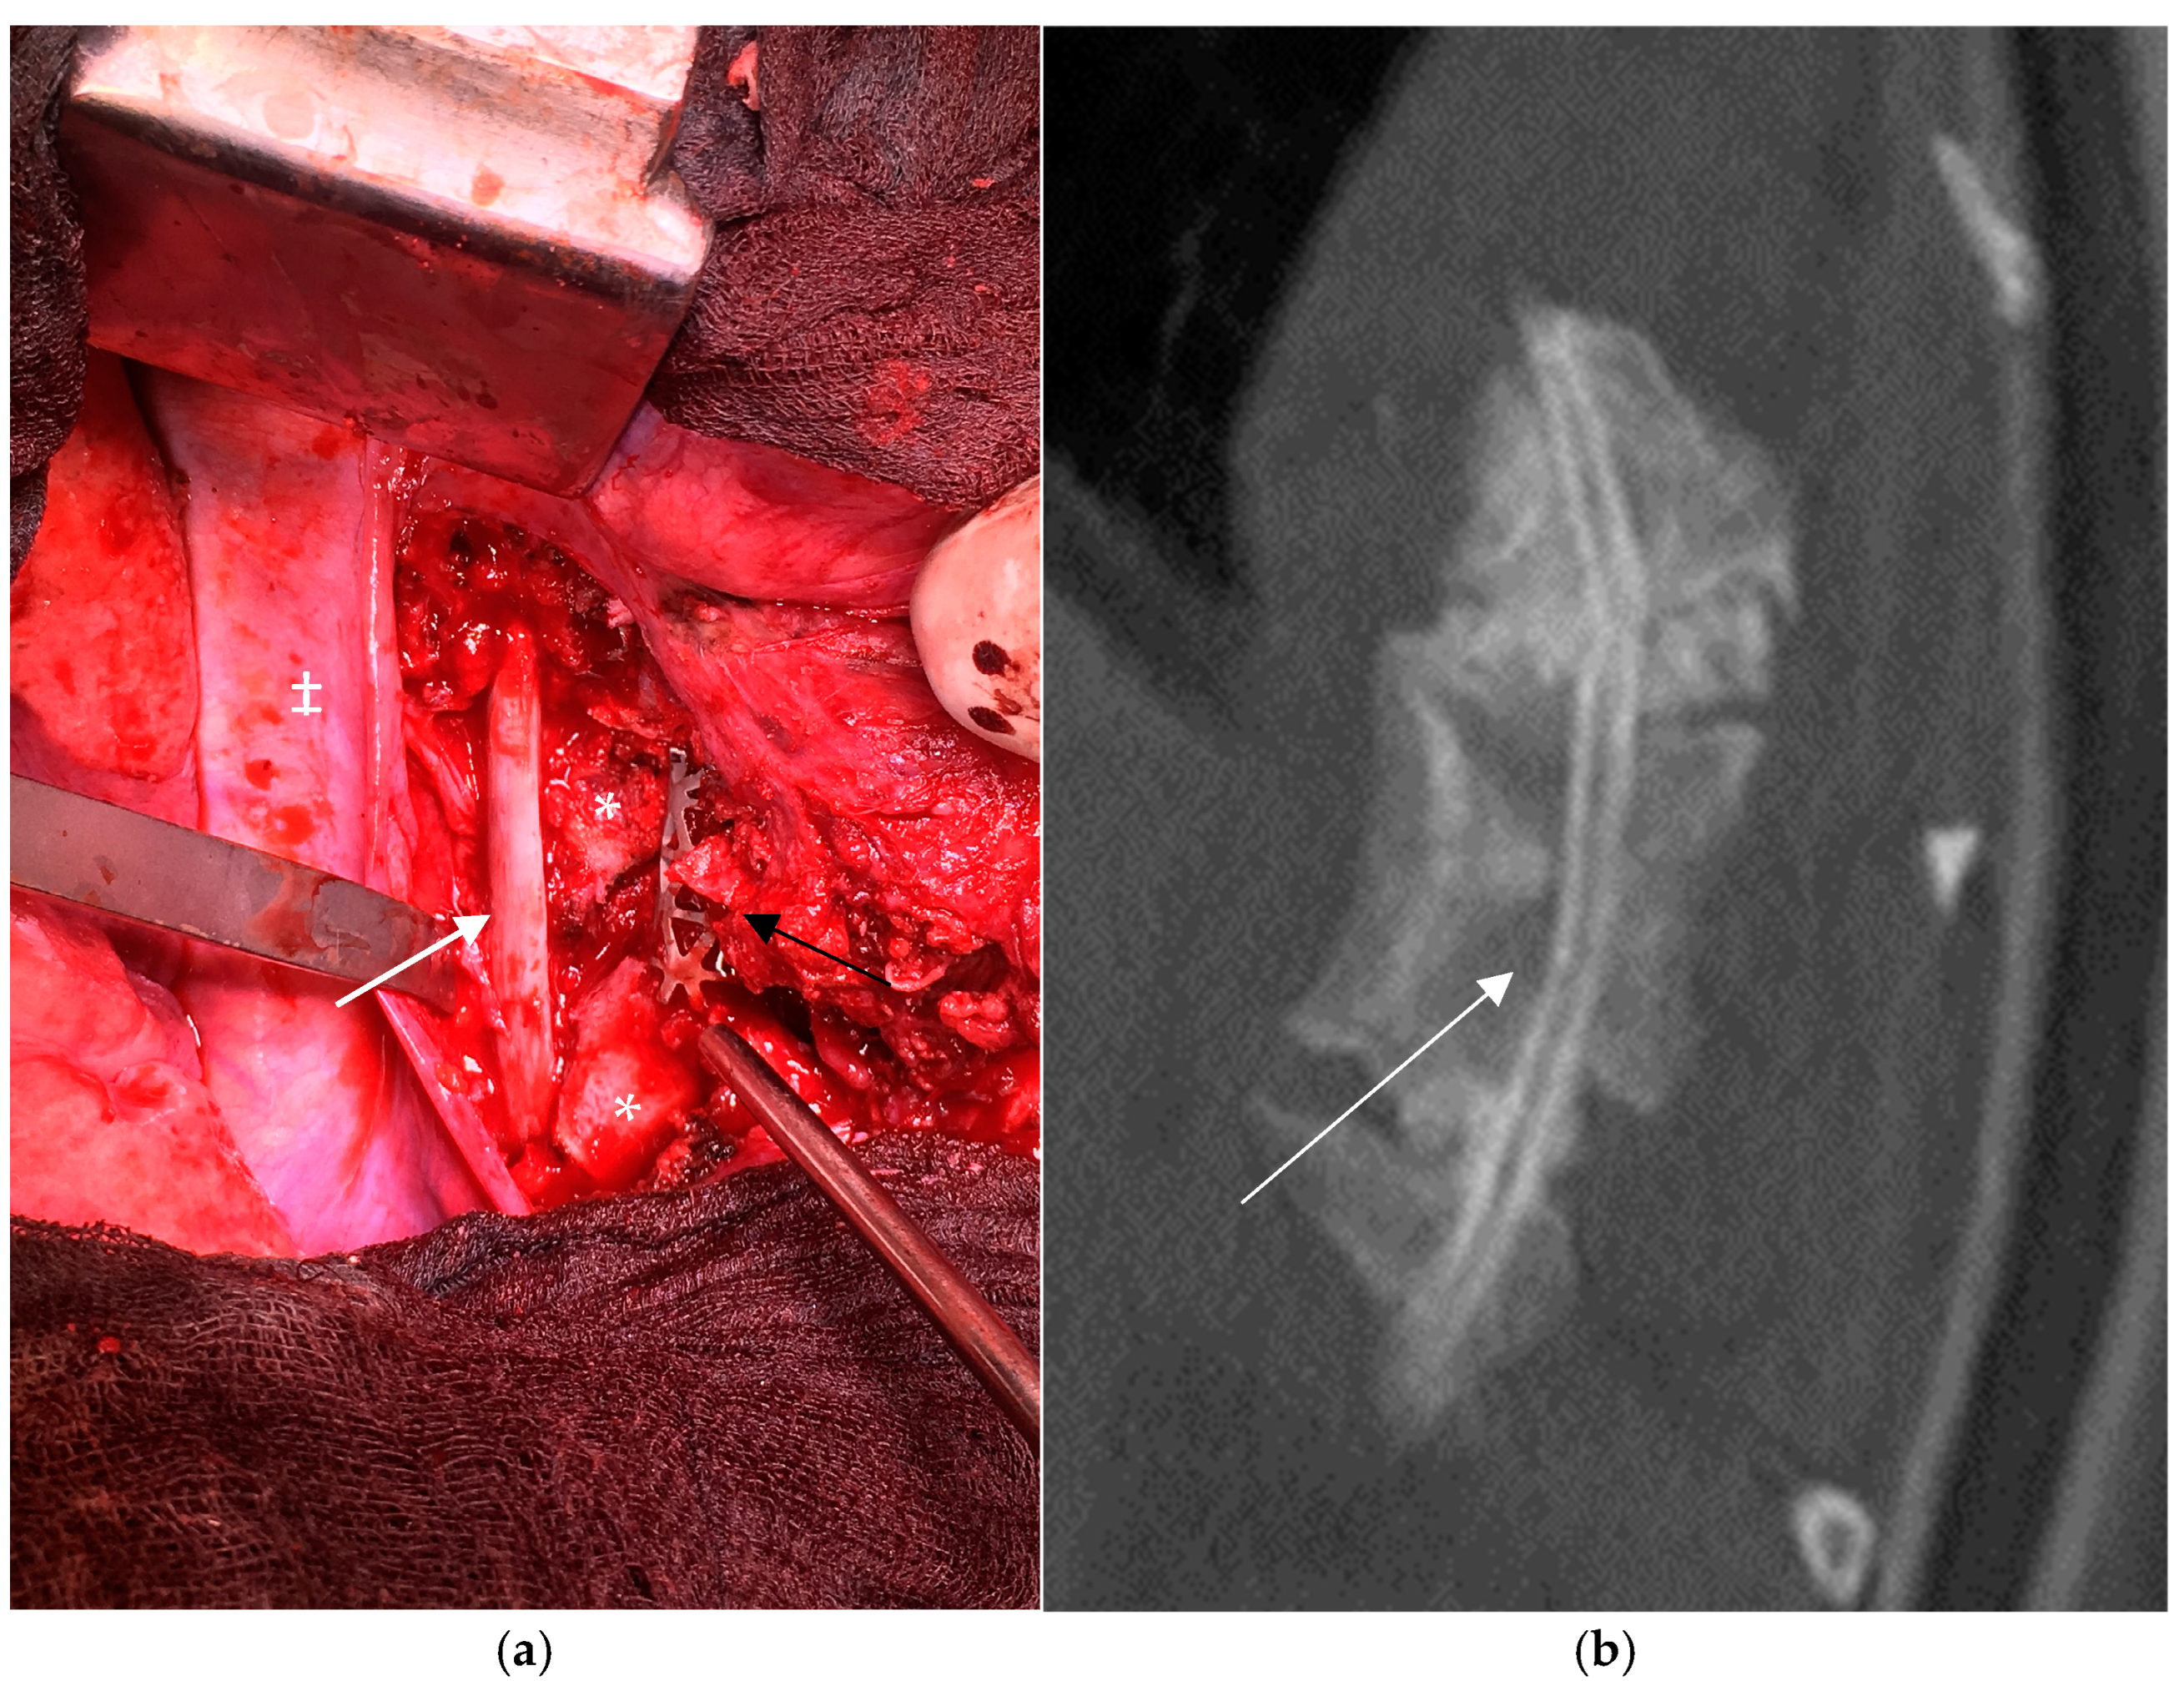

4.1. Cervical Spine

5.1. Cervical Spine